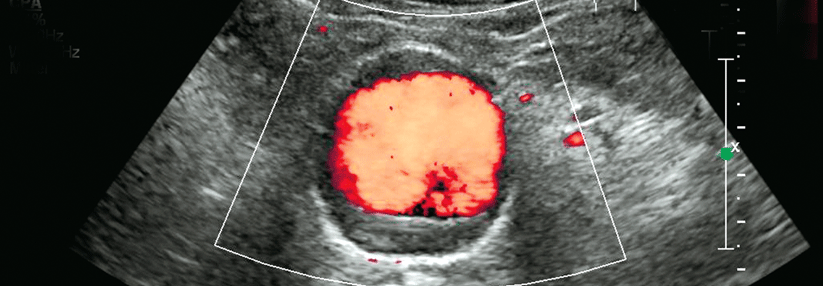

Da der Trend insgesamt Richtung endovaskulärer Aortenreparatur geht, sind die beobachteten Geschlechterunterschiede bei diesem Verfahren bedenklich, so die Autoren. Über die Ursachen der Differenzen könne man derzeit nur spekulieren. Möglicherweise existieren für Frauen einfach keine passenden Stentgrafts, da sich ihre Befunde anatomisch oft komplexer präsentieren – z.B. mit einem kürzeren und schmaleren Aneurysmahals.